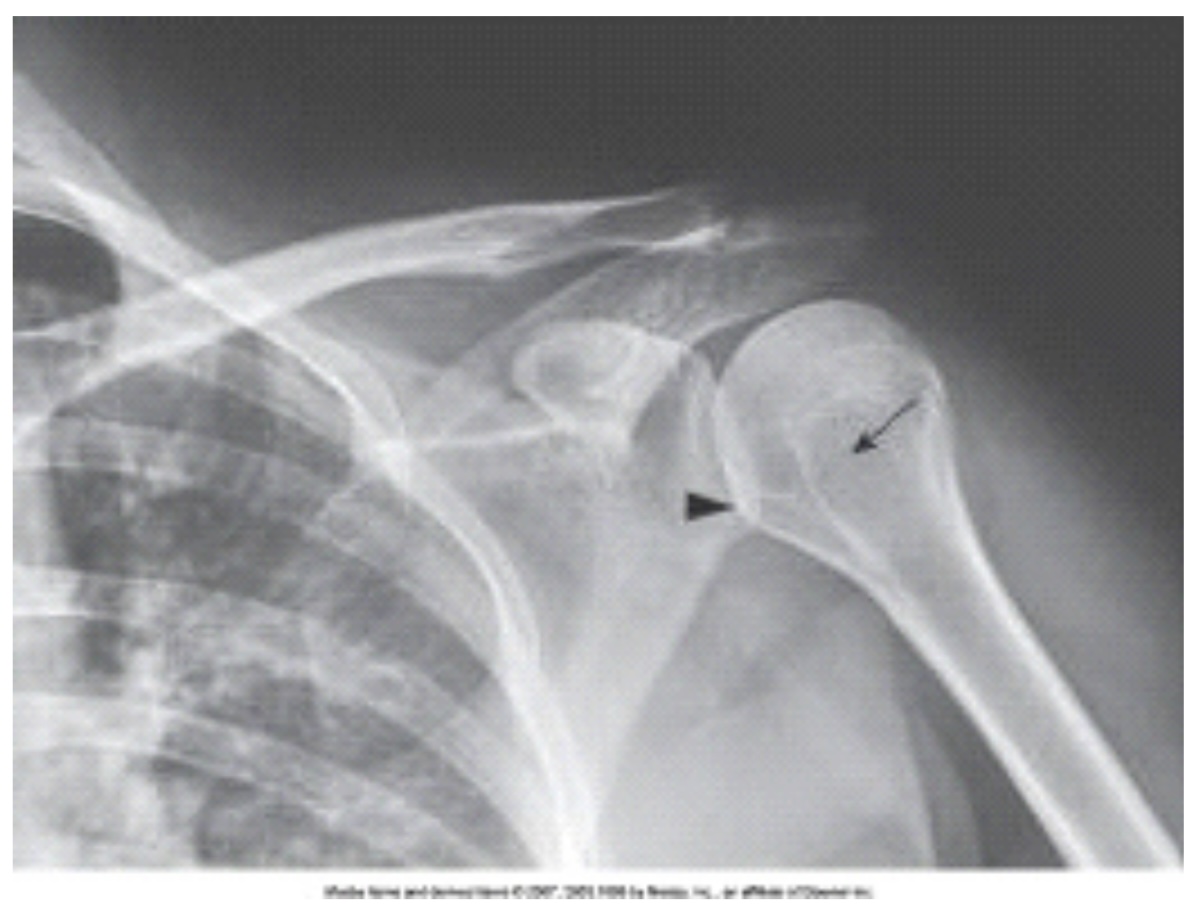

What projection, position, and anatomy of interest in the image below is demonstrated?

AP projection of the shoulder in internal rotation

The anatomy labeled in the image below by the arrowhead is the:

lesser tubercle.